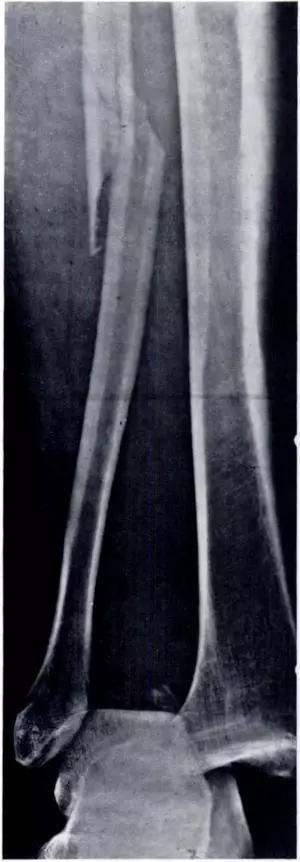

11. Nightstick 骨折(警棍骨折)

直接外伤造成尺骨单骨折。前臂单纯的尺骨骨折,通常是由钝伤造成。Nightstick 的意思是警棍,此伤害可因受到棍击时举起手来抵挡产生。

(来源:Radiopaedia)